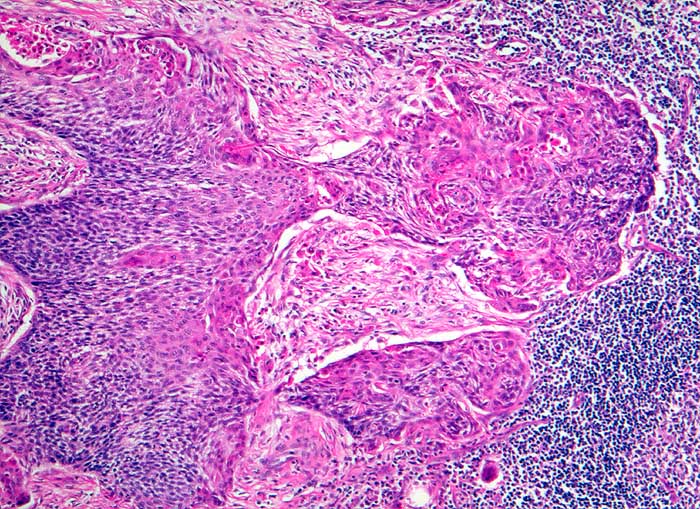

PathoPic ID 5508 - Plattenepithelkarzinom: Lymphknotenmetastase

Plattenepithelkarzinom: Lymphknotenmetastase

maligner Tumor

Lymphknoten, Kopf-cervikal

Lymphatische Gewebe, KM, Milz

Solide, auf weiten Strecken basaloide Tumorzellstränge umgeben von desmoplastischem Stroma infiltrieren den Lymphknoten.

3cm grosser Tumor Hals rechts

Histologie

50